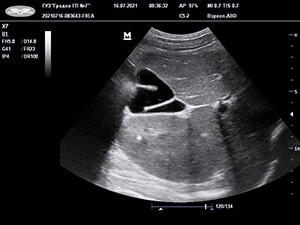

Рисунок. S-образные формы желчного пузыря. Результаты УЗИ.

Застой желчи, или билиарный сладж, у детей визуализируется в виде взвеси гиперэхогенных частиц; другие варианты крайне редки. Конкременты выявляются независимо от возраста (даже у пациентов до 3 лет).

УЗИ является одним из основных методов диагностики аномалий развития и приобретенных деформаций желчного пузыря, в то же время в диагностике аномалий протоковой системы данное исследование не всегда информативно.